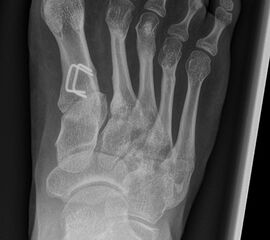

MT I Basis closed wedge Osteotomie

Besteht bei einem Kind oder Jugendlichen ein Hallux valgus mit einer Überlänge Metatarssale I, kann minimalinvasiv eine adduzierende closing wedge Osteotomie lateral basisnah durchgeführt werden (Abb. 24).

Abb. 24 a-d: Röntgen präoperativ bei Hallux valgus und dezentrierten Sesambeinen mit Schmerzen seit einem Jahr unter dem Großzehengrundgelenk (a), druckentlastende minimalinvasive Metatarsale I closing wedge Osteotomie an der Basis (b), intraoperative Korrekturstellung (c) und intraoperatives Bild nach Entfernung der Kirschner-Drähte sechs Wochen postoperativ (d).